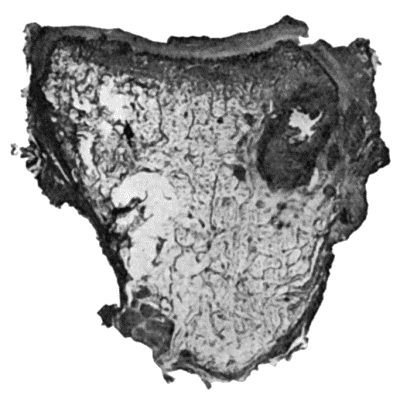

| 114. | Section through Gouty Bursa | 428 |